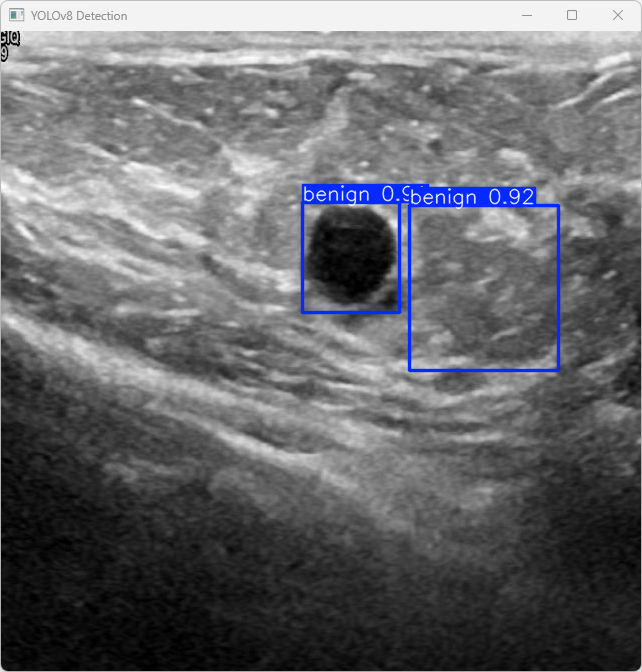

执行imgTest.py代码后,会将执行的结果直接标注在图片上,结果如下:

这段输出是基于YOLOv8模型对图片“imagetest.jpg”进行检测的结果,具体内容如下:

图像信息:

(1)处理的图像路径为:TestFiles/imagetest.jpg。

(2)图像尺寸为 640×640 像素。

检测结果:

(1)模型在该图片上检测到 2 个良性结节(”2 benign”)

处理速度:

(1)预处理时间:3.2 毫秒

(2)推理时间:4.1 毫秒

(3)后处理时间:45.7 毫秒

模型在处理图片时非常高效,成功检测出2个良性结节,并将结果保存到了指定目录。